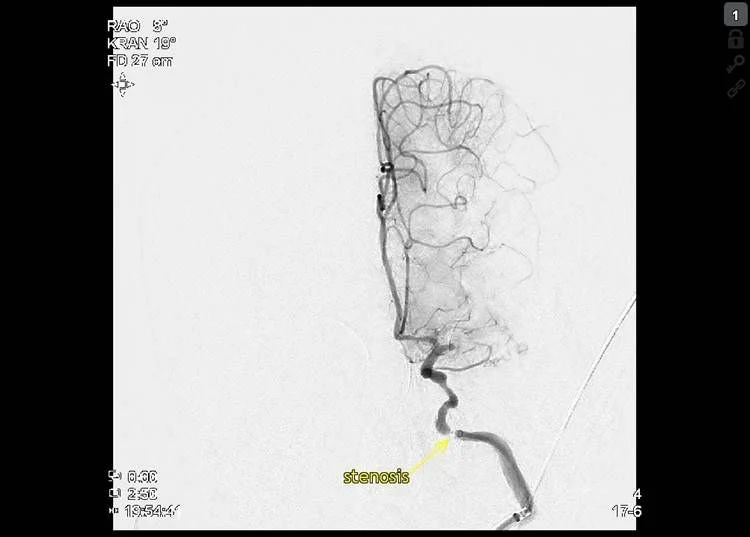

Stroke CT workup showed 16 ml well delignated infarct of the head of caudatenucleus and putamen (ASPECTS 8), a proximal left M1 occlusion and 40 ml of perfusion lesion in the MCA territory (18:25, Brainomix). No thrombolysis.

Thrombectomy was done with Embovac and Tigertriever (Rapid Medical) in general anaesthesia (door-to-groin 109 min, 19:44) with first pass recanalization TICI 2c in 16 min (20:00, door-to-final-TICI 123 min).